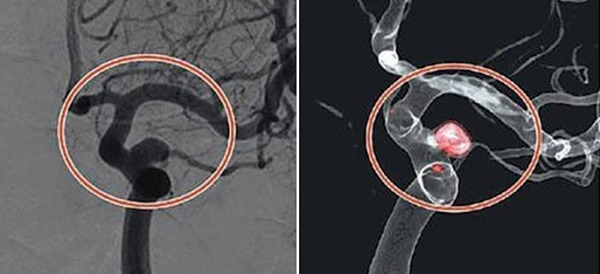

뇌혈관 조영술은 대퇴동맥을 통해 카테터라는 2mm 내외의 관을 삽입한 후 조영제를 주입하고 X-ray를 촬영하여 뇌혈관의 상태를 파악하는 검사입니다. 이 검사는 뇌동맥류, 뇌혈관 협착, 뇌동정맥 기형 등의 진단에 매우 정확하며, 치료 계획을 세우는 데 필수적입니다.

코일색전술은 뇌를 열지 않고 혈관 내에서 동맥류를 치료하는 방법으로, 대퇴동맥을 통해 삽입한 카테터를 이용하여 동맥류 내부에 백금 코일을 채워 혈류를 차단하는 시술입니다. 이를 통해 동맥류의 파열을 방지할 수 있습니다.